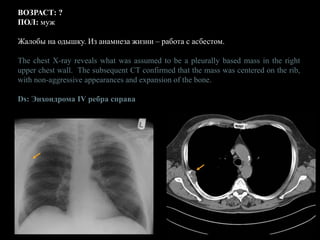

ВОЗРАСТ: ?

ПОЛ: муж

Жалобы на одышку. Из анамнеза жизни – работа с асбестом.

The chest X-ray reveals what was assumed to be a pleurally based mass in the right

upper chest wall. The subsequent CT confirmed that the mass was centered on the rib,

with non-aggressive appearances and expansion of the bone.

Ds: Энхондрома IV ребра справа